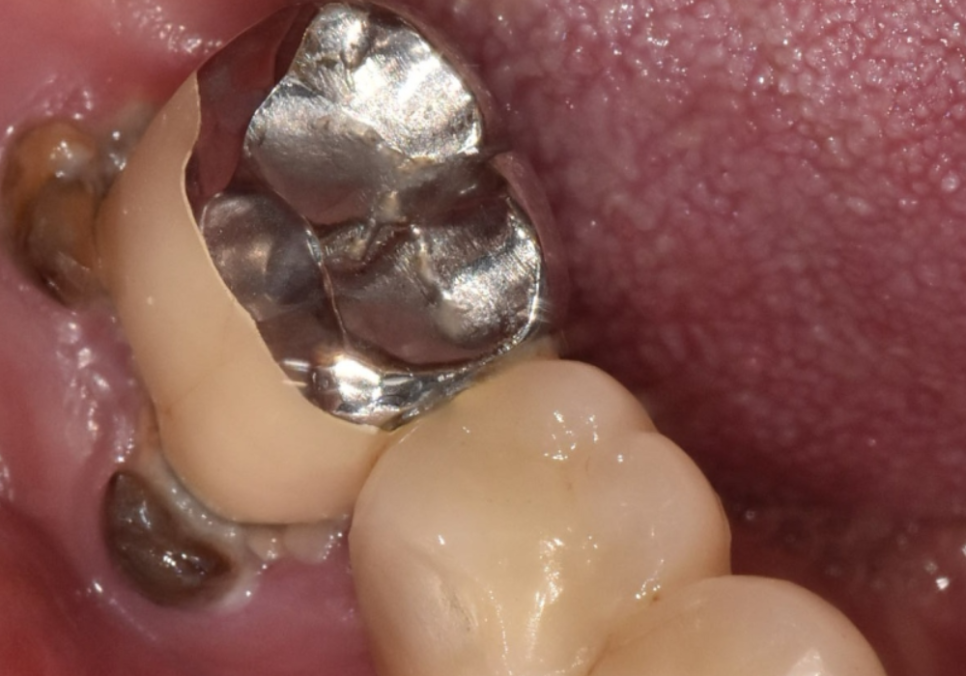

자세히 살펴보니, 잇몸 쪽으로

치아 뿌리가 살짝 드러나 있고

그 틈으로 음식물이

끼어있는 모습이 관찰되었죠.

엑스레이를 찍어보니 상황은

생각보다 더 심각했습니다.

보철 내부가 이미 다 삭아서

치아 머리와 뿌리가 툭 끊어져 있는 상태였거든요.